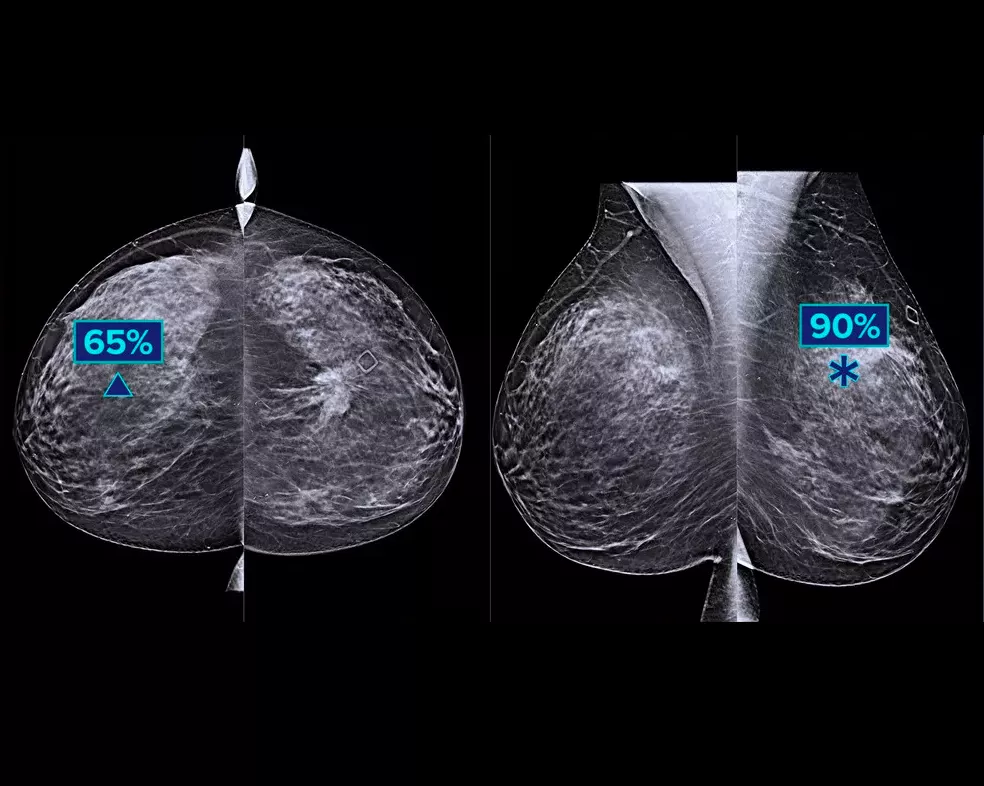

Powered by AI, Intelligent 2D imaging technology produces robust, yet natural looking, synthesized 2D images that are well correlated with the 3D mammography data. This enables radiologists to quickly and confidently see subtle mammography features and lesion morphology.*

Retain more features of interest from high-resolution 3D mammography data. Use AI-powered analytics to confidently visualize subtle tissue features and lesions in the reconstructed, synthesized 2D images.

- Exceptional 2D image contrast, sharp images with enhanced background and localized density appearance to enable FFDM-like representation of parenchymal tissue at 70μm resolution.

- Move from suspicious areas detected on the 2D image to the point of interest on the 3D mammography slice.